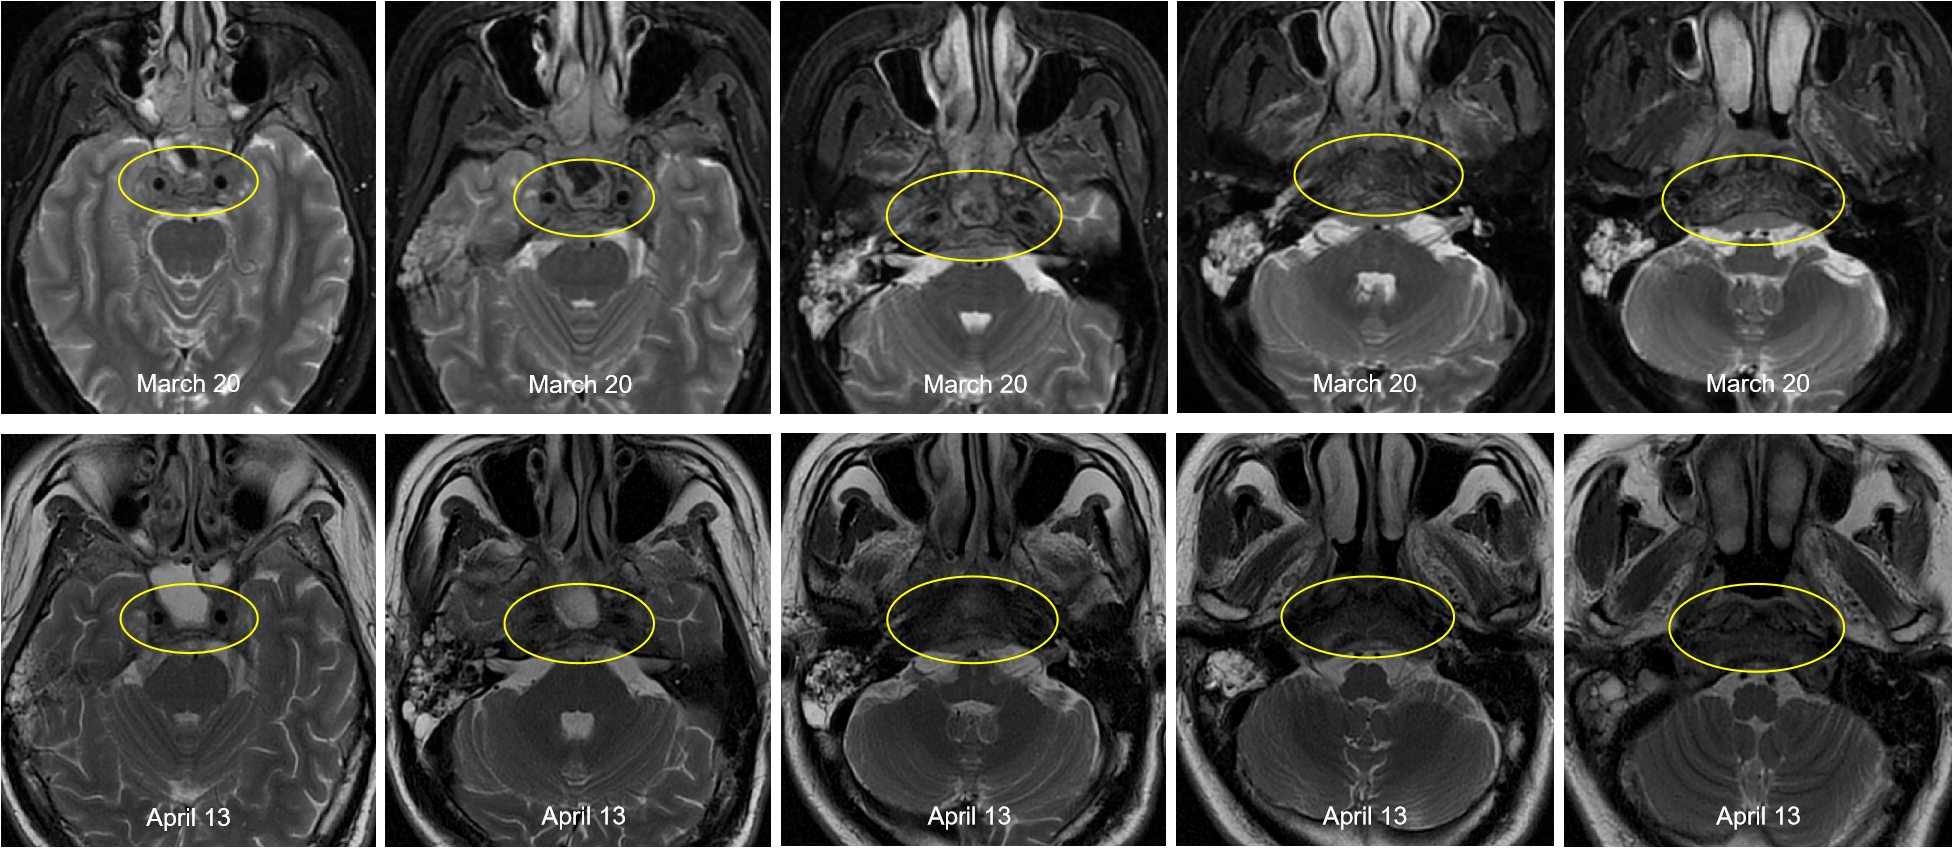

This patient was diagnosed with nasopharyngeal non-keratinizing squamous cell carcinoma (T4N2M1, stage IVB, AJCC 8th), which had indications of palliative chemoimmunotherapy, and we obtained informed consent from patients and families for all of our treatments. Therefore, the planned therapeutic regimen consists of gemcitabine (at a dose of 1 g/m2 on days 1 and 8) and cisplatin (40 mg/m2, days 1-2), plus tislelizumab (200 mg on day 1). Alleviation of reported symptoms was observed following the first dose, potentially reflecting treatment-induced tumor volume reduction and subsequent decreased mass effect on adjacent neural structures. But, on day 3 post-treatment, i.e. on March 29, the patient developed recurrent fever, peaking at 39.2 °C. He also developed severe paroxysmal stabbing pain in the right frontal area suggestive of trigeminal neuralgia, accompanied by increased numbness on the right face. The NRS pain score was 9. His labs were notable for high C-reactive protein (CRP) at 117.46mg/L. His blood culture results (e.g., bacteria and fungi) were negative. The fever is considered to be caused by a bacterial infection (gemcitabine administration on day 8 of the first cycle was withheld due to fever); however, it persisted despite antibiotic therapy, which included cefoperazone and ceftriaxone. After administration of dexamethasone, symptoms were not relieved, and morphine failed to provide adequate analgesic effect. To assess for pulmonary infection and evaluate whether tumor progression is contributing to the clinical deterioration, chest CT and cranial MRI were performed. The CT (April 6) revealed no significant infectious foci (Supplementary Figure 2). The MRI (April 13) demonstrated a slight reduction in tumor size compared to previous imaging (Figure 3).

Figure 3

Comparison of pre- and post-treatment imaging showed a slight reduction in tumor size following chemoimmunotherapy.